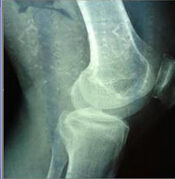

其病理特點為關節軟骨變性、破壞,軟骨下骨硬化、關節邊緣和軟骨下骨反應性增生、骨贅形成。